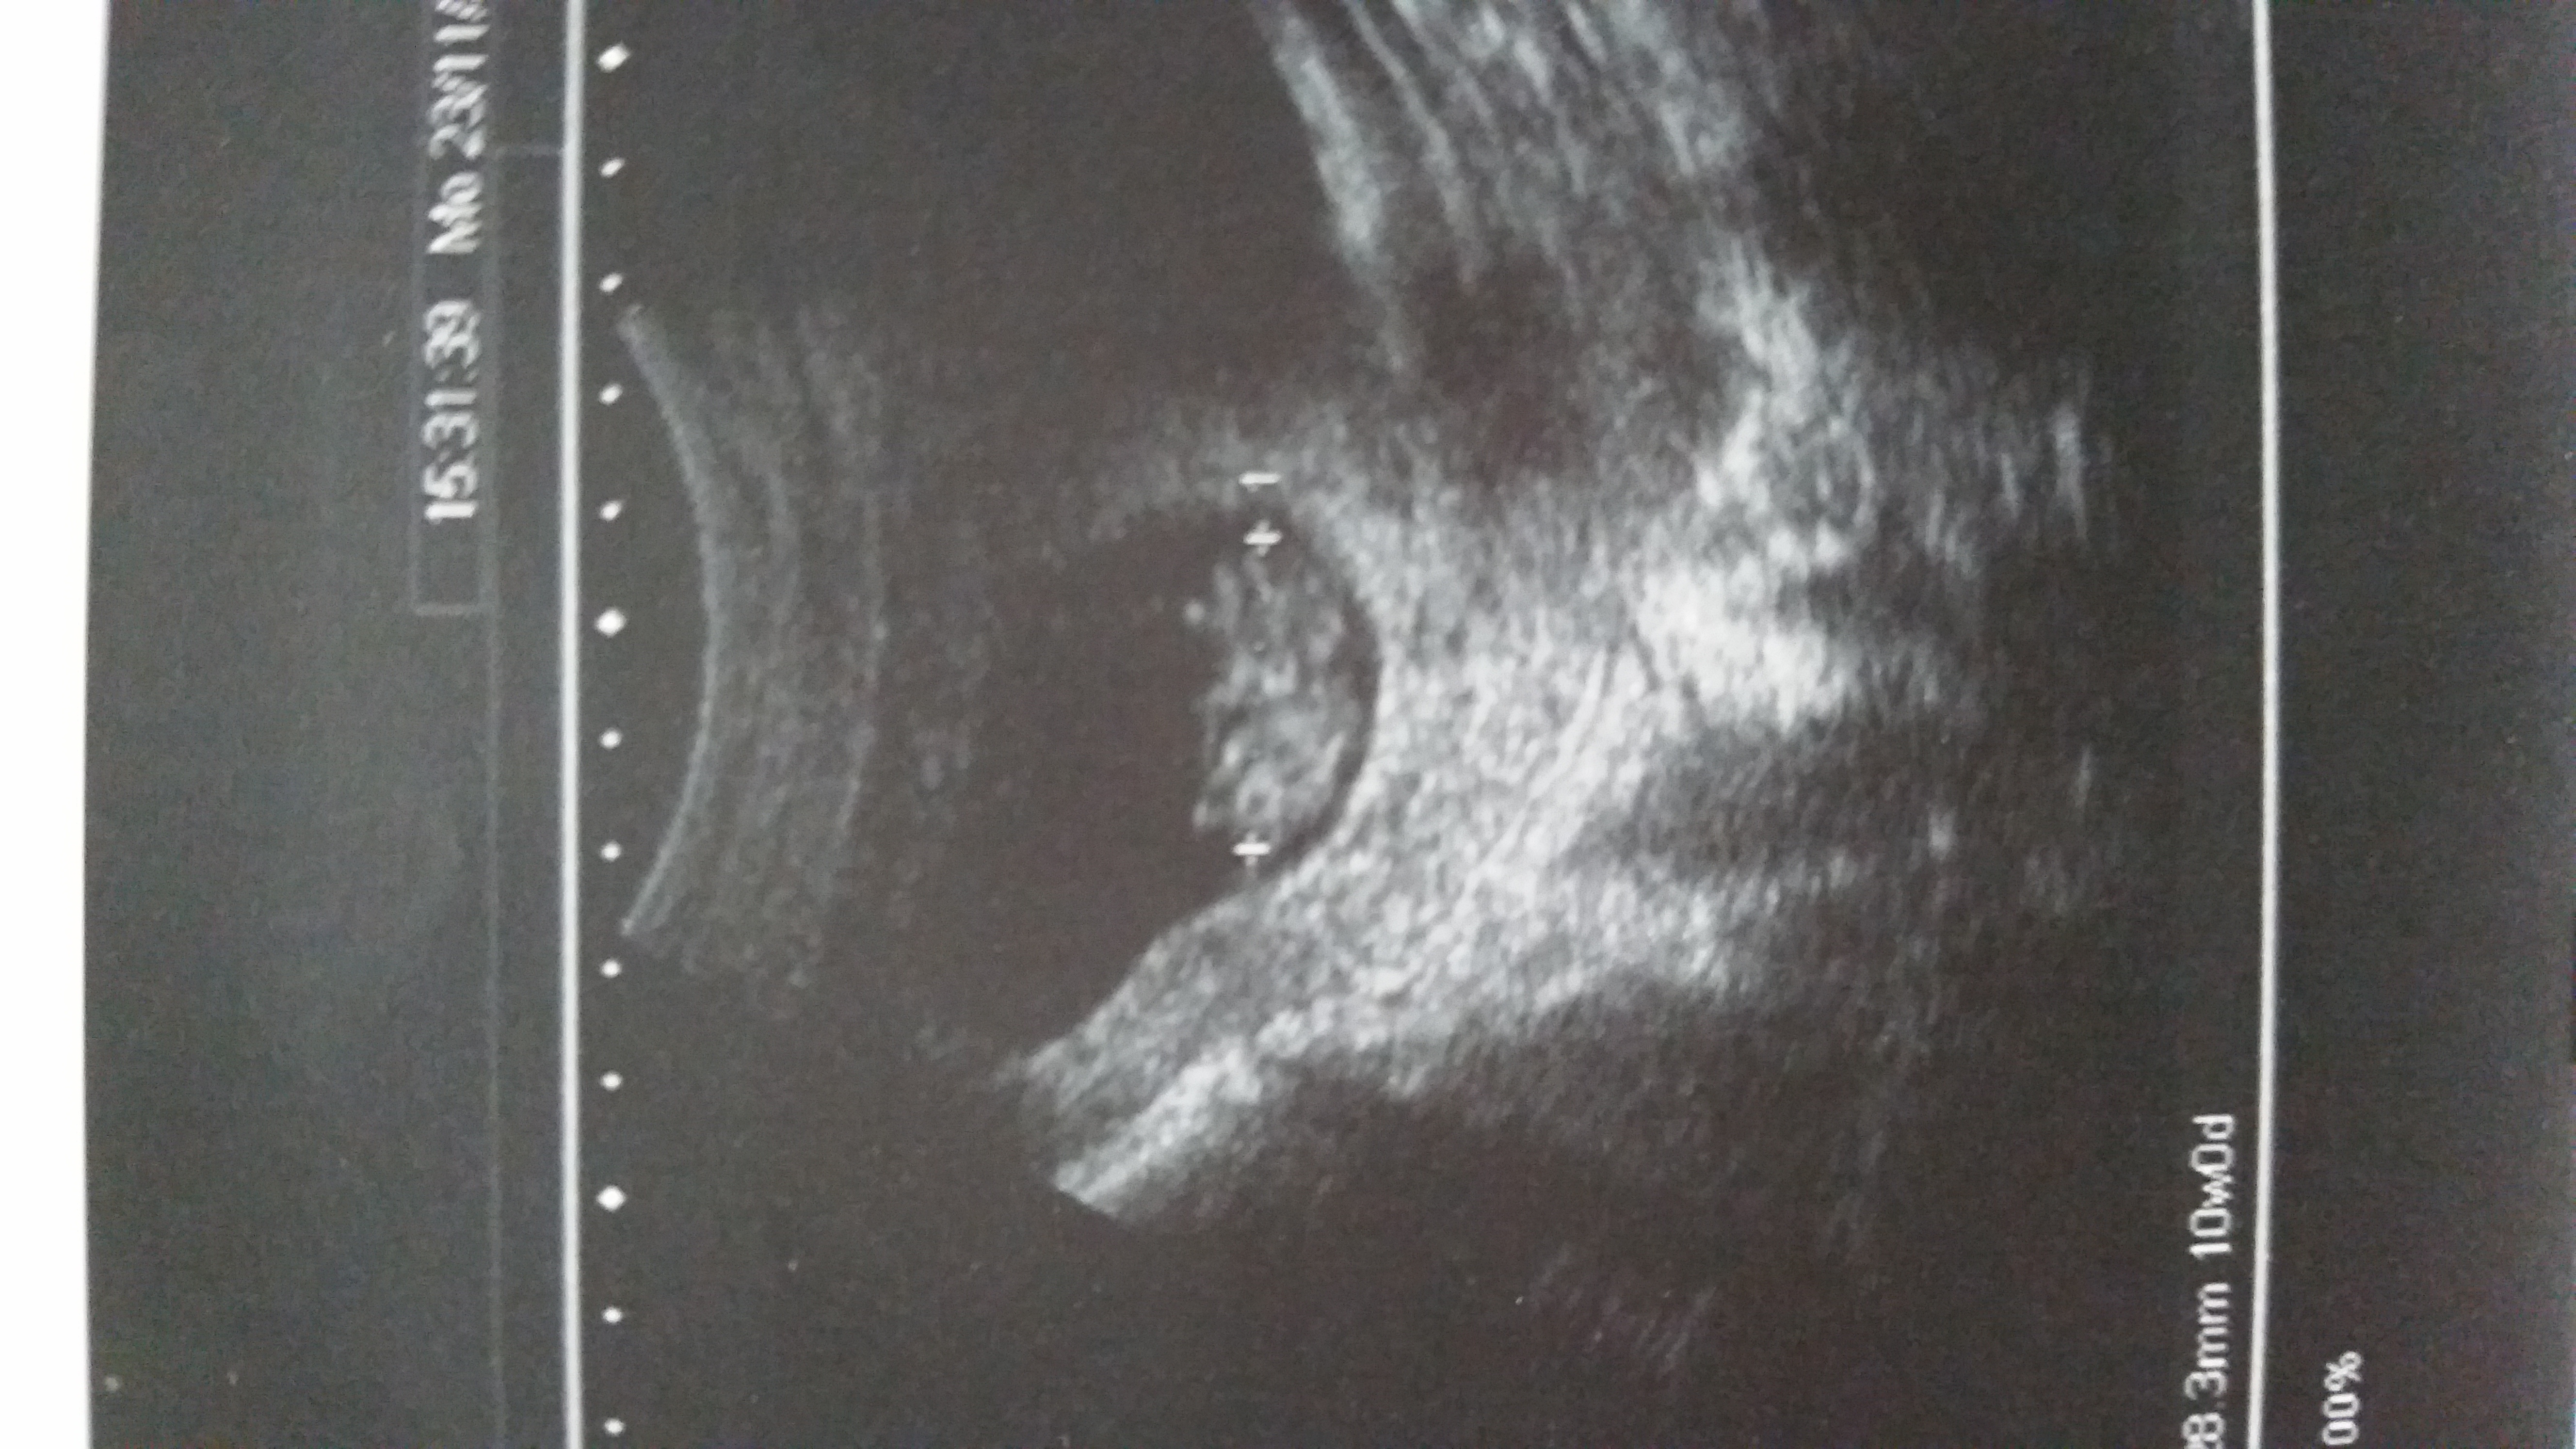

• 10 weeks US 176BPM it's amazing to see how much s/he moved!

I have a gender determination 3D ultrasound scheduled for Dec 17th (14w5d). Any thoughts if that's too early? The office told me they can do it as early as 12 weeks!?